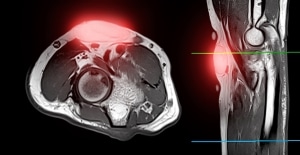

במידה ועולה חשש, ויש צורך באבחון נפנה לבדיקת MRI שהיא בדיקת הדימות המתאימה לבירור אופי הרקמה. בבדיקה זו ניתן יהיה להבחין בין רקמת שומן תקינה לממאירה.

סריקת ה-MRI מגלה נגע ליפומה במפרק המרפק, המודגש על ידי האזור האדום